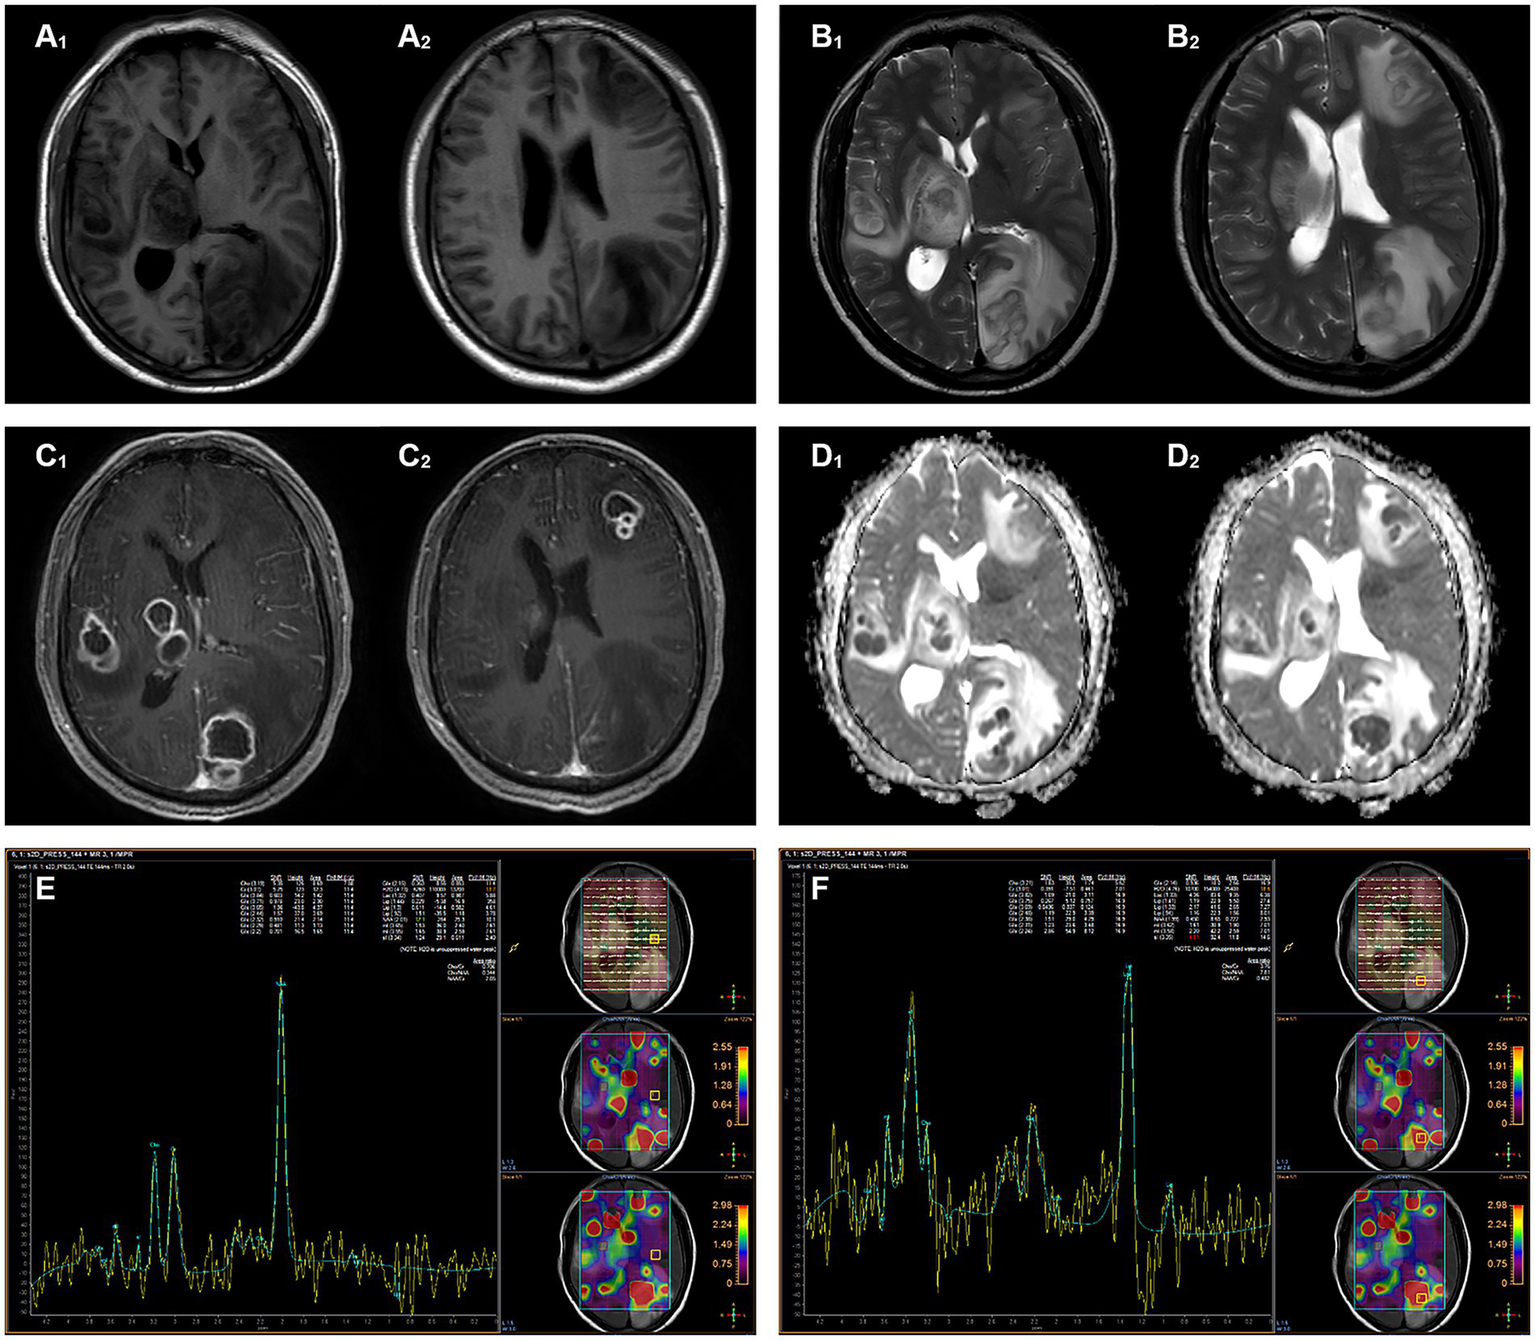

Head magnetic resonance imaging (MRI) indicated multiple lesions in the left frontal lobe, parietal occipital lobe, temporal lobe, right temporal lobe, thalamus, and brain stem with low signal intensity on T1-weighted imaging, high signals on T2-weighted, and hyperintensity on T2-weighted fluid-attenuated inversion recovery (FLAIR) sequences. Diffusion-weighted imaging (DWI) revealed distinct hyperintense regions centrally within the lesions, corresponding to hypointense regions on apparent diffusion coefficient (ADC) mapping. Patchy edema was observed around the lesions, with the largest lesion located in the left parieto-occipital lobe, measuring about 35 mm × 23 mm. Mild localized compression of the third ventricle and left lateral ventricle was noted, along with a partial midline shift to the left. The peripheral enhancement of multiple lesions was observed after contrast administration. Magnetic resonance spectrum (MRS) showed spectral alterations consistent with multiple intracranial lesions (Figure 1).

Figure 1

Magnetic resonance imaging shows multiple intracranial lesions. (A₁,A₂) The lesion areas demonstrate hypointense and isointense on T1WI. (B₁,B₂) The lesion areas demonstrate hyperintense and isointense on T2WI. (C₁,C₂) The signal intensity of the ring wall was increased after enhancement. (D₁,D₂) DWI hyperintensity with ADC hypointensity, the lesion shows true diffusion restriction. (E) MRS shows normal metabolite peaks within the normal area. (F) MRS of the lesion demonstrates a pathological spectrum, suggestive of abscess.

Cranial imaging, including CT or MRI, can help to identify brain abscesses, which typically manifest as ring-enhancing lesions. Functional MRI enables us to distinguish from other annular enhancement lesions such as tumors, cystic foci, or necrotic foci (3, 30, 31). In the present case, the patient was hospitalized due to symptoms such as headache, nausea, and left walking. Both PET-CT and MRI showed multiple focal images with enhanced annular edges. In addition, the DWI of lesions showed significant diffusion restriction with high signal intensity, and corresponding regions showed low signal intensity on ADC. Based on these findings, the patient was diagnosed with multiple intracranial abscesses.